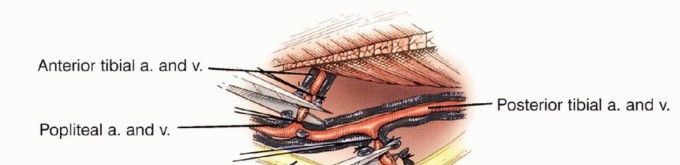

تفرع الشريان المأبضي

يتفرع الشريان المأبضي إلى الشريان الظنبوبي الأمامي، والشريان الظنبوبي الخلفي، والشريان الشظوي عند الحافة السفلية للعضلة المأبضية. يتكون هذا التفرع في الواقع من تفرعين: الأول حيث ينشأ الشريان الظنبوبي الأمامي من الشريان المأبضي، الذي يستمر بعد ذلك كجذع ظنبوبي شظوي. أما التفرع الثاني فيوجد حيث ينشأ الشريان الشظوي والشريان الظنبوبي الخلفي من الجذع الظنبوبي الشظوي، أي أنه يقع بعيداً عن الشريان الظنبوبي الأمامي.

من الضروري تقريباً ربط الشريان الظنبوبي الأمامي أثناء الاستئصال، بينما يجب تحديد الأوعية الأخرى بعناية قبل ربطها. تتميز العضلة المأبضية بكونها تغطي السطح الخلفي لقصبة الساق، مما يوفر حاجزاً ممتازاً بين امتداد الأنسجة الرخوة الخلفية من قصبة الساق والحزمة الوعائية العصبية للطرف السفلي. هذه الميزة التشريحية الفريدة والمحظوظة تختلف عما يحدث في عظم الفخذ البعيد، حيث يتم تغطية الجانب الخلفي فقط بالدهون المأبضية.

يُستخدم تصوير الأوعية ثنائي المستوى (Angiography) لتقييم الشرايين المحلية، خاصة إذا كشف التصوير المقطعي المحوسب عن امتداد الورم إلى الأنسجة الرخوة الخلفية. تُستخدم الرؤية الأمامية الخلفية لتقييم تفرع الشريان المأبضي، مع التركيز بشكل خاص على سلامة الشريان الظنبوبي الخلفي، والذي قد يكون المصدر الوحيد لإمداد الدم للساق بعد الاستئصال.

تُعد الرؤية الجانبية ضرورية لتقييم المسافة بين قصبة الساق والحزمة الوعائية العصبية. على سبيل المثال، غالباً ما تفصل العضلة المأبضية كتلة الورم الخلفية عن الأوعية الدموية. ينعكس هذا كمسافة واضحة في تصوير الأوعية الجانبي، ويشير إلى وجود هامش استئصال كافٍ. غالباً ما يكون ربط الشريان الظنبوبي الأمامي ضرورياً. قد يتأثر الشريان الشظوي بالأورام التي تشغل حجرة خلفية كبيرة. في المرضى الشباب، يمكن ربط اثنين من الأوعية الرئيسية دون تعريض إمكانية بقاء الطرف حياً وظيفياً للخطر. نادراً ما يتأثر الشريان الظنبوبي الخلفي بالورم.

استكشاف الحفرة المأبضية والحزمة الوعائية

يجب استكشاف تفرع الشريان المأبضي مبكراً لتحديد ما إذا كان الورم قابلاً للجراحة، خاصة إذا كانت مكوناته في الأنسجة الرخوة تمتد خلفياً. إذا لم يكن هناك امتداد خلفي، يتم تعريض الفراغ المأبضي والتفرع عن طريق فصل العضلة التوأمية الإنسية وشق العضلة النعلية. يمكن تحديد الشريان المأبضي بسهولة وتتبعه بعيداً حول العضلة المأبضية. يجب توخي الحذر لتحديد وحماية جميع الفروع الوعائية الرئيسية.